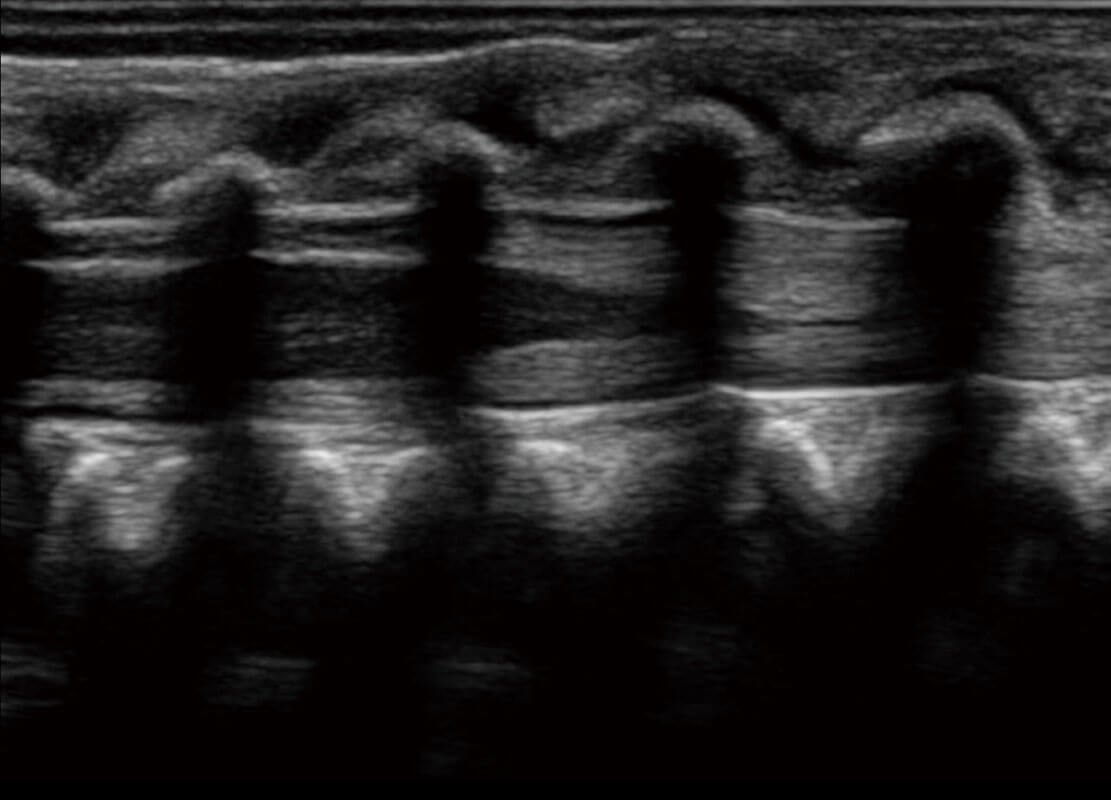

• 新生儿脊髓圆锥

• 新生儿心脏